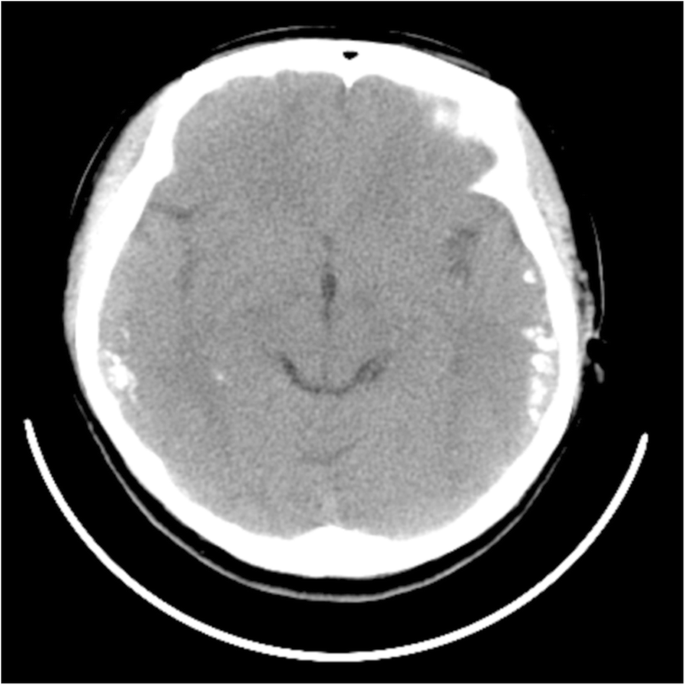

Six months after the second admission, the patient’s condition remained stable. We found that her CSF antibody titers turned negative. However, two weeks later, her initial symptoms recurred. Laboratory screening results were normal but, the screening of CSF showed it was again anti-NMDAR antibody-positive (1:1, cell-based assays, Euroimmun, Germany). Additionally, mild growth of bilateral temporal calcifications was detected by CT (Fig. 3). The MRI of the brain showed that the cortical swelling had subsided significantly compared to the second admission. Gynecological ultrasound revealed the absence of a tumor. Serum folate levels were within the reference range. As aforementioned, cerebral calcifications were a significant specific feature of our patients. Many diseases, including CEC, can cause cerebral calcification and epilepsy. We reviewed the medical history of the patient in detail, including the abdominal symptoms. The patient reported that she had chronic diarrhea, of which her uncle and brother also had a history, and abdominal pain. To determine whether she had CD, we analyzed her serum for anti-autoantigen (tTG) antibodies (including antigliadin and antiendomysium antibodies), but the results were negative. She declined further investigation by duodenal endoscopic biopsy. We considered she was in a stable phase of CD, but still recommended that she had to adhere to a strict GFD. In the following ten months, the patient’s conditions gradually improved. The patient underwent chest and abdomen CT and pelvis ultrasound, no teratoma was found, and she returned to normal work and life activities.